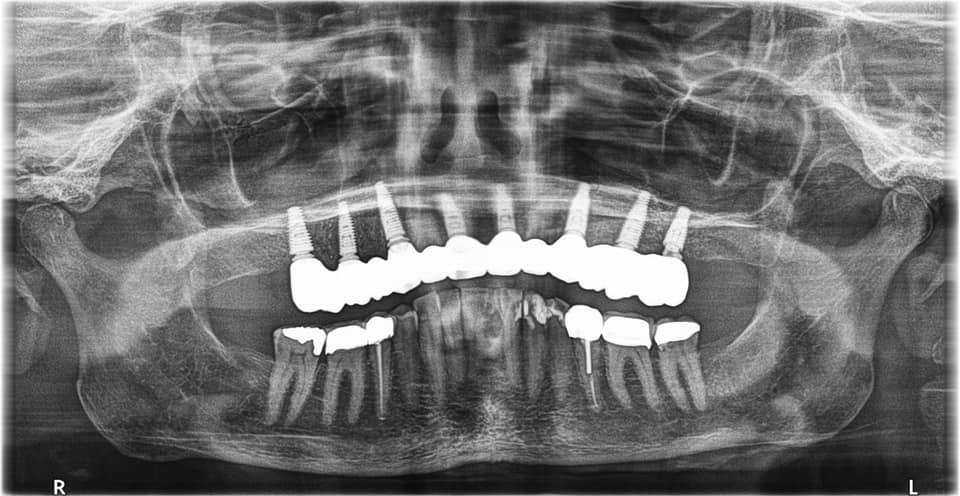

Below is a case of full arch same day temporization using the socket shield , root submergence and pontic shield techniques to preserve the site architecture . Neodent GM implants were placed in a guided fashion and same day temporization was performed using a milled PMMA.

The final bridge was constructed in monlithic zirconia.

-Immediate load temp upper